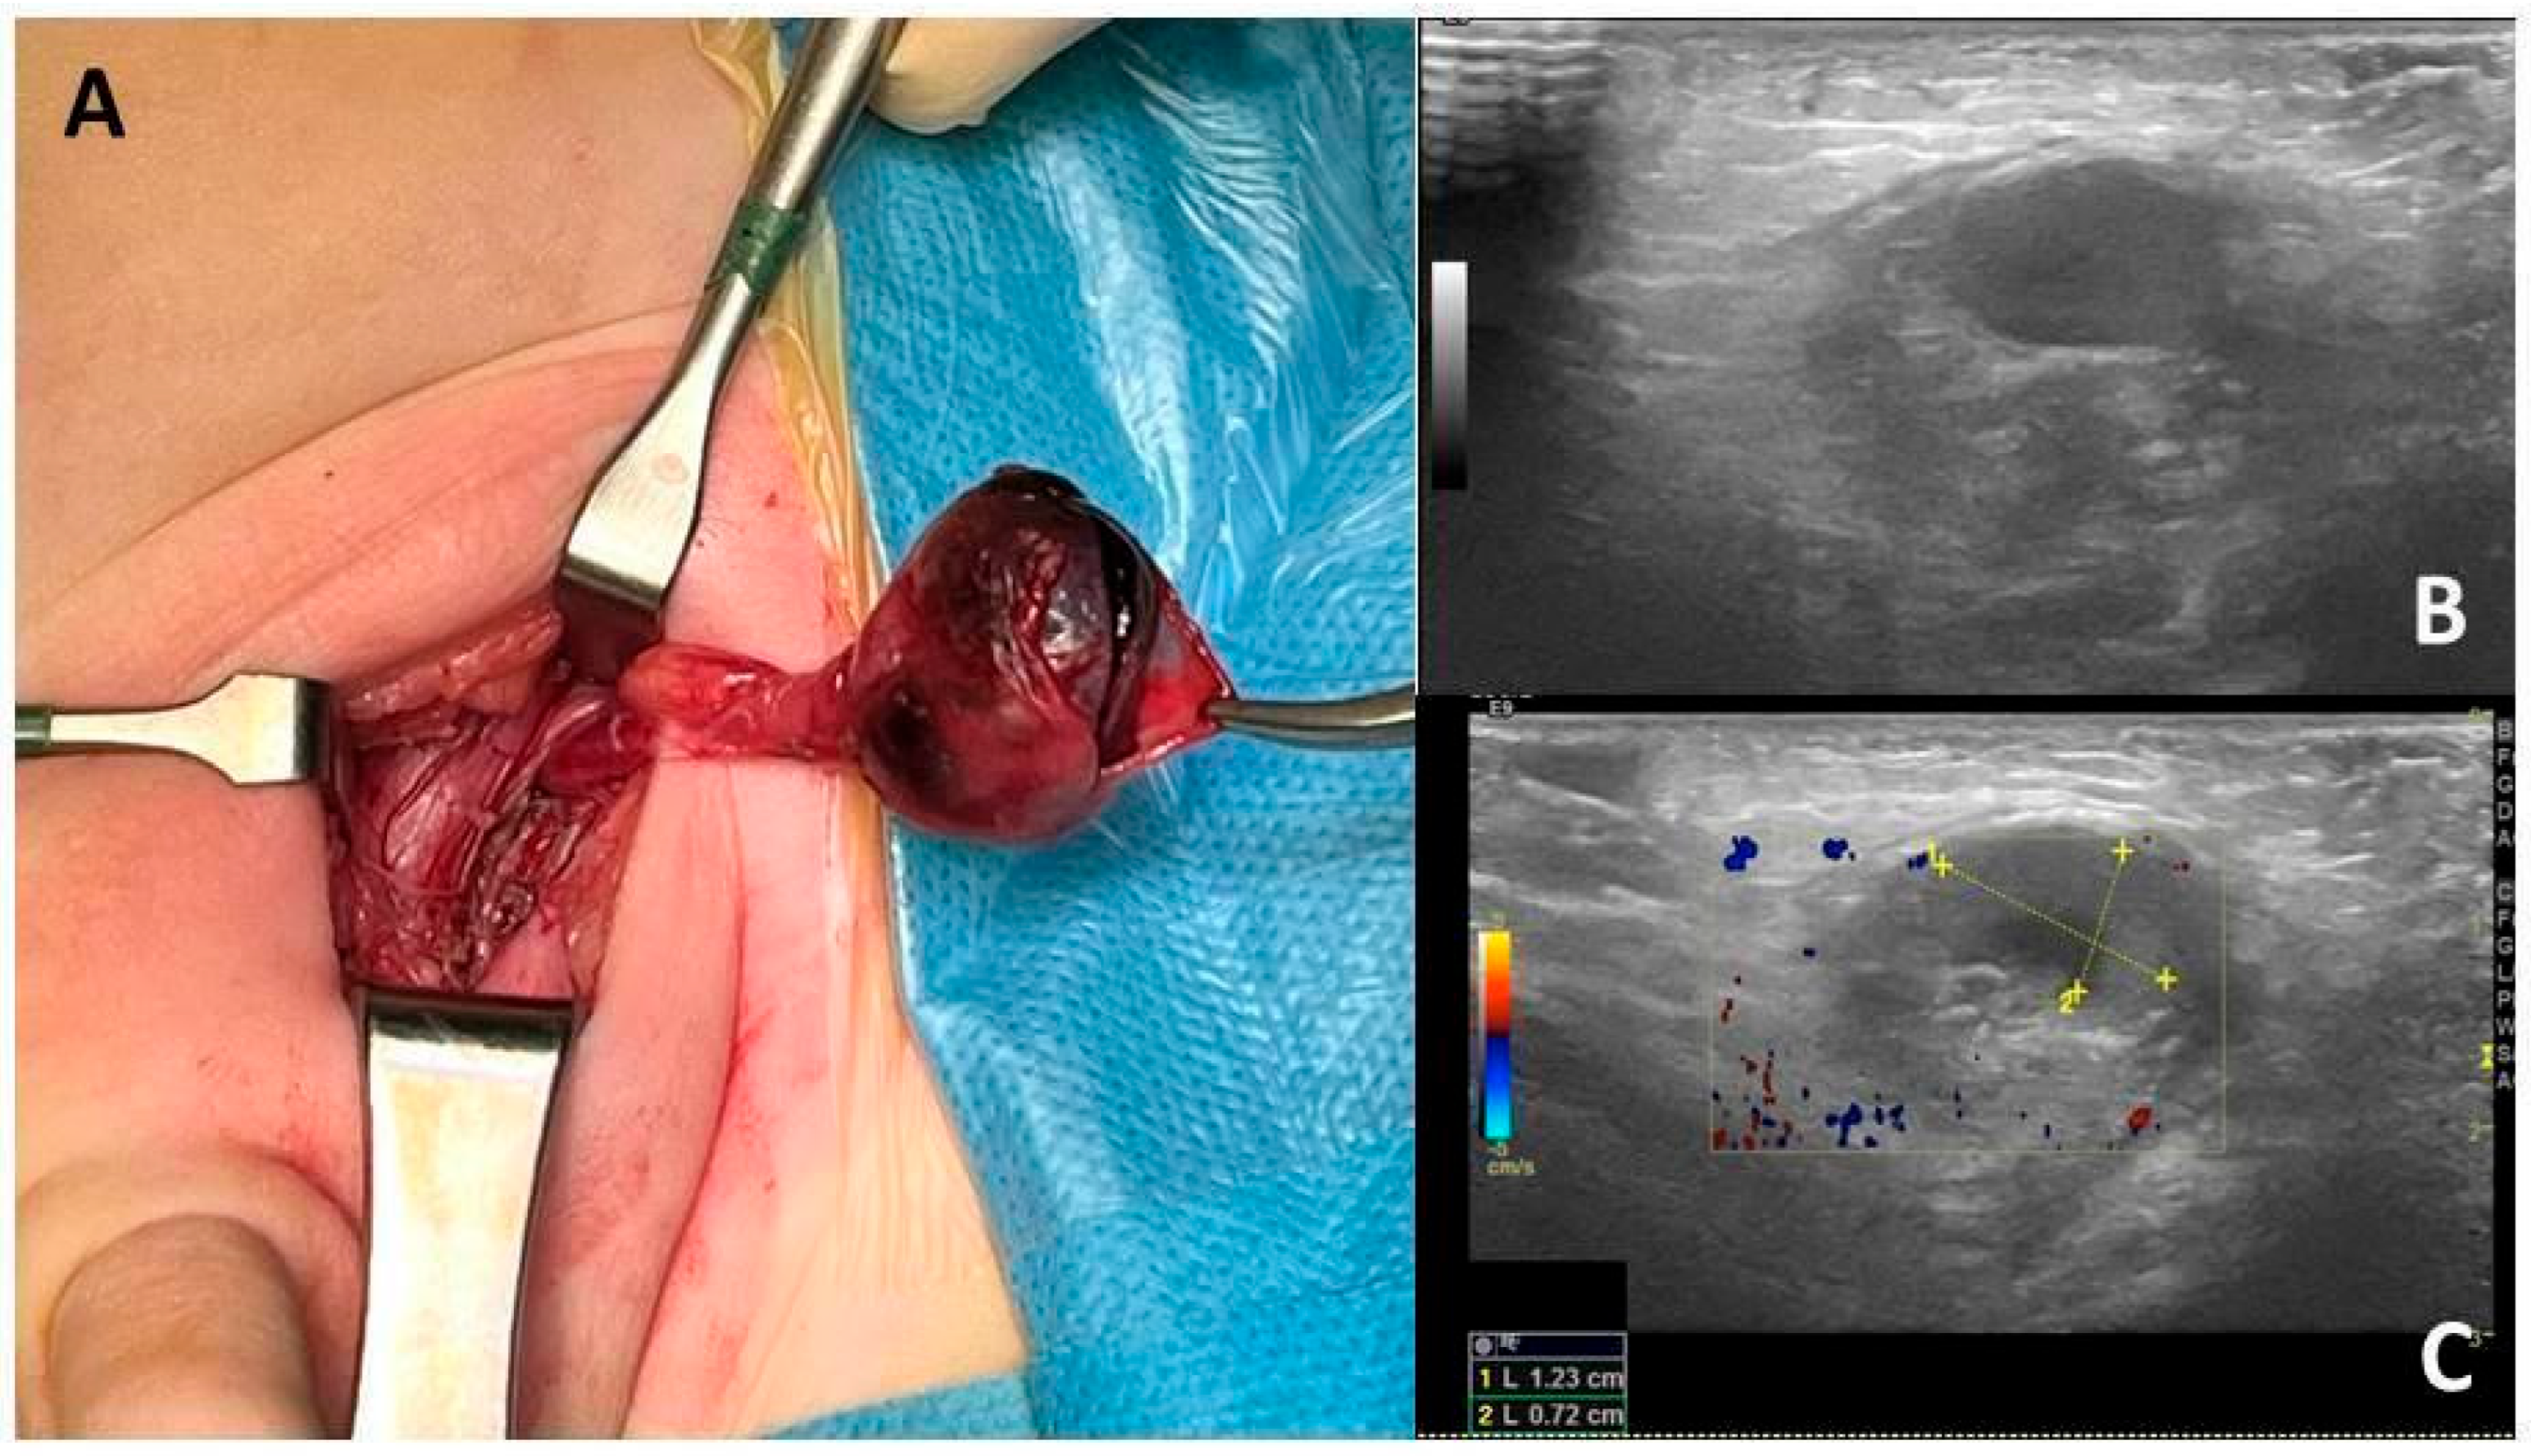

| Baldanza et al. | 10 | L | 36 h | Inconsolable crying, inguinal swelling, and pain | Orchiectomy |